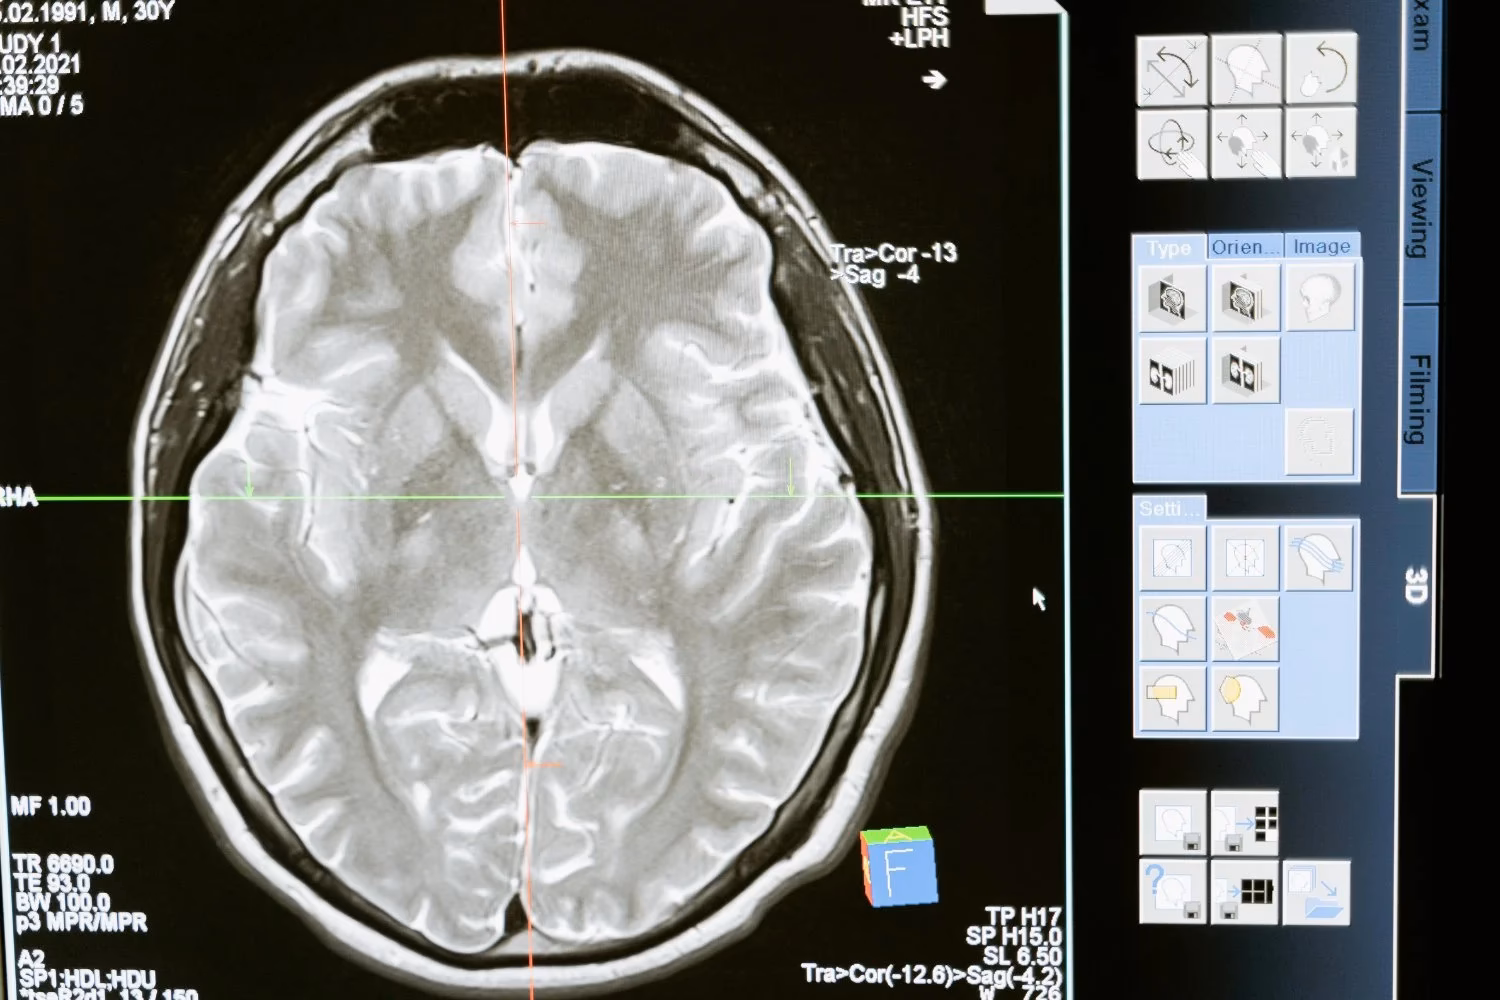

El cuidado de una lesión medular comienza desde el momento del accidente, con acciones de emergencia cruciales como la inmovilización de la columna. En el hospital, el enfoque inicial es estabilizar al paciente, mantener funciones vitales y prevenir complicaciones como infecciones o coágulos sanguíneos. Las herramientas de diagnóstico como rayos X, tomografías computarizadas (CT) y resonancias magnéticas (MRI) son esenciales para evaluar el daño. El tratamiento agudo puede incluir tracción para alinear la columna o cirugía para descomprimir la médula. Aunque medicamentos como el metilprednisolona se usaron en el pasado, las investigaciones recientes desaconsejan su uso rutinario debido a los riesgos.